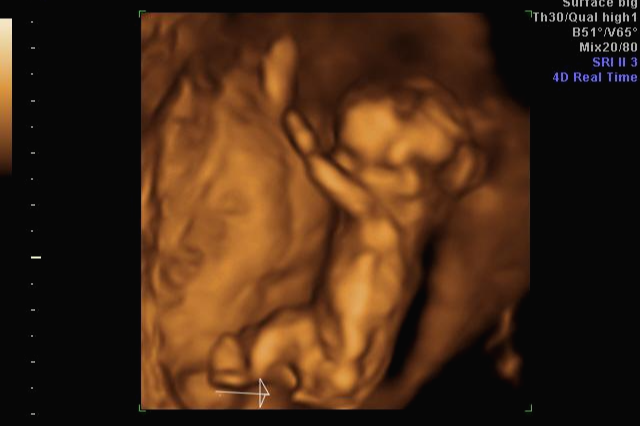

24주 차에 다시 사설로 초음파 검사를 받으러 갔는데 초음파를 보시더니 정밀 초음파 검사 때 성별 딸이 었냐 아들이 었냐 물어보시길래 딸이라고 말을 하니 미안하다고 지금 보니 딸이라고 하길래 이때는 정밀 초음파 검사 후 한 달 뒤여서 상관없다고 ㅋㅋㅋㅋㅋ 아들인지 딸인지 뭐가 중요하냐고 아이만 건강하면 된다고 하니 ㅎㅎ 그때서야 웃으시더라고요 ㅎㅎ 많이 미안했던 모양... 워낙 아이 건강상태를 꼼꼼하게 잘 봐주시고 만족할만하게 아이 얼굴 초음파 사진을 찍어주셔서 다 용서가 됐어요 ㅎㅎ

내 뱃속에 이렇게 사랑스러운 아이가 있다니 >. < 이렇게 이쁜 아이를 보면 성별반전은 중요하지 않아요~

입체 초음파 사진은 항상 만족스러워요! 사진 보면 벌써 태어난 아기처럼 어찌 이리 이목구비 뚜렷하고 아이 얼굴이 선명하게 잘 보이는지~ 제아이라 이렇게 사랑스러운 걸까요~? ㅋㅋㅋ